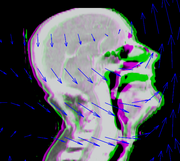

Anatomic change due to tumor regression in nasopharyngeal cancer

Head and neck cancers account for about 60,000 new cancer cases per year and represent about 6% of all cancers in the United States. These cancers are treated by a combination of chemotherapy, radiotherapy, and surgery. The five-year survival is approximately 50%. During a six-week regimen of radiotherapy, head and neck cancer patients often exhibit anatomic changes that affect their treatment. These changes include tumor regression or growth, changes in lymph node size, and changes in air cavities. Uncorrected, these changes can increase the risk of treatment complications or reduce treatment efficacy.

Adaptive radiotherapy is a form of personalized medicine that addresses the problem of anatomic change by incrementally adjusting the radiotherapy plan. However, a mid-treatment adjustment is complex: it requires a new CT image, image segmentation, deformable registration, and mapping of the previously delivered dose onto the new image. This project proposes to use the NA-MIC Kit to develop a simple, practical workflow for achieving personalized adaptive radiotherapy.